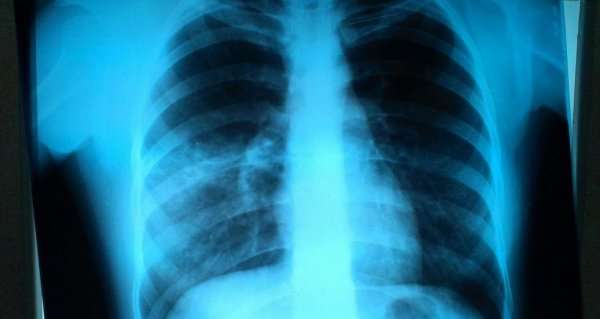

Рентгеновское и флюорографическое исследование имеют один и тот же принцип, но при диагностике пневмонии предпочтение отдается рентгену.

Фото2

Флюорография позволяет выявить изменения в тканях легких на ранних стадиях, но не дает достаточно четкой рентгенологической картины для постановки точного диагноза.

Вместе с тем, коэффициент облучения при проведении процедуры гораздо меньше, чем при рентгеновском исследовании, поэтому флюорографию делают в профилактических целях, а рентген – непосредственно для диагностики патологических процессов при наличии соответствующих симптомов.